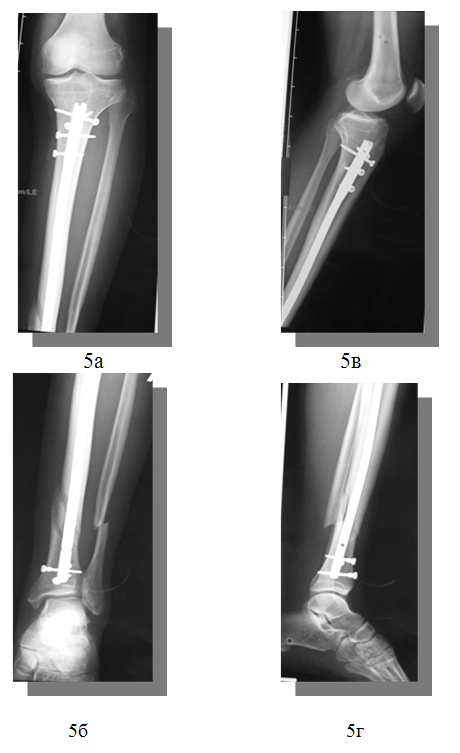

2) закрытый винтообразный перелом нижней трети левой большеберцовой и малоберцовой костей со смещением отломков.

Операция: Репозиция, остеосинтез левой большеберцовой кости интрамедуллярным блокированным штифтом «Expert» Synthes.